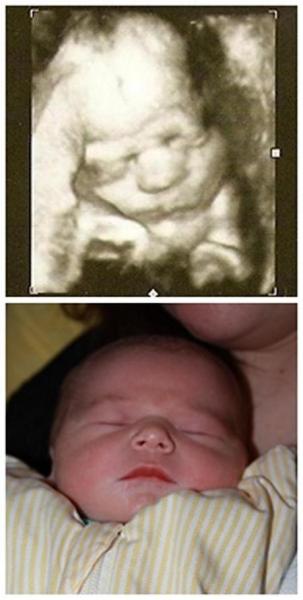

Ich muss echt sagen, dass ich erstaunt bin, wie genau ein 3D Ultraschallbild zeigt, wie das Baby aussehen wird!!! Ich habe zwei Bilder gegenübergestellt: einmal aus der 36.SSW (35+0) und beim Anderen ist Cian 1Tag alt (21.August)!!!

Schaut und staunt!!!